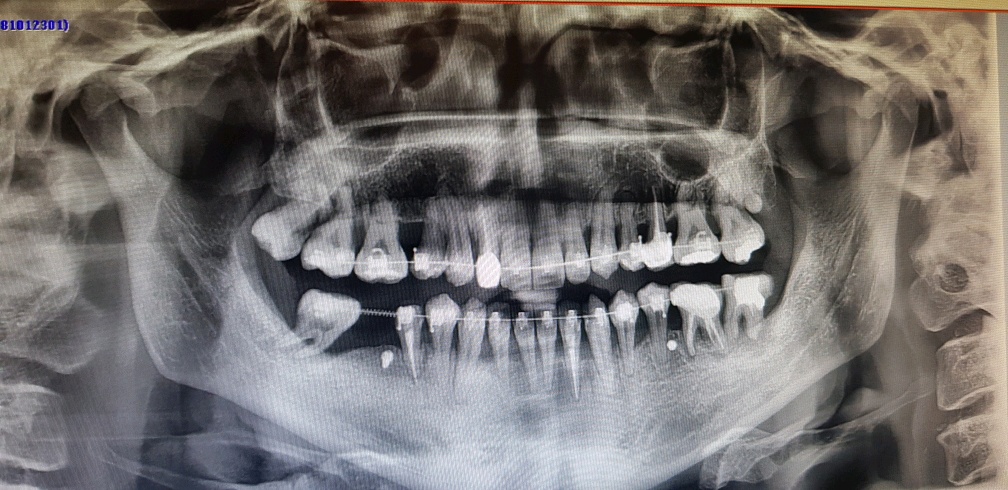

이게 몇일 전 찍었던 엑스레이 사진인데

그래도 처음보다 상당히 낳아진 치아 상태죠;;

오른쪽 윗쪽 어금니 부분 보면 사랑니가 튀어나와있는게 보일겁니다.